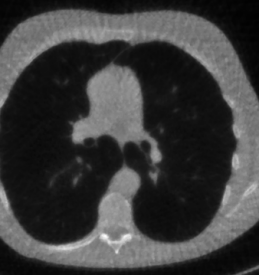

Here we present the results of RISING applied to the Mayo data set introduced in paragraph 4.1. As previously mentioned, we consider two sparse-view CT geometries, namely and . In Figure 4 we report the results for the protocol, achieved on one image of our test set. The top-left image represents the reconstruction. Even if only a small number of iterations are performed, the main structures of the abdomen are visible; however, the image is still blurry. In the image, shown in the upper-right corner, we notice that the TV regularizer has acted to totally eliminate the artifacts and noise, improving the uniformity of the image in the inner structures. When compared to the ground-truth solution in Figure 2, the contours of the details in appear slightly jagged, differently from where they are neat but, usually, corrupted by artifacts. The bottom row of Figure 4 shows the two and images, respectively from left to right. It is evident that has retrieved many details but it presents noisy components, reflecting the features of its target image . Our solution is less corrupted, since the low-contrast regions are correctly preserved and the noise is not visible. These observations are confirmed by Figure 5, which plots the intensity profiles taken over the red line in the second crop (Figure 2). In our approach (on the right) the CNN has accurately learnt the map of (8) and the red profile mostly overlaps the black one. On the contrary, the profile (on the left) is more distant from its target reference.

We now consider the CT protocol whose results are reported in Figure 6.

In this case, the tomographic reconstruction is more challenging than in the previous experiment. The starting image has evident streaking artifacts and blur and some details are lost, especially in the first zoom. The artifacts are reduced in the (top right image), where some details are recovered and the edges are quite neat.

The image obtained with the proposed RISING (bottom right) is visually an excellent reconstruction. It is very similar to the image, whose training, we remark, is based on more informative target images.

In Figure 7 we plot for these experiments, the same profiles of Figure 5.

In the left graph, we analyse the performance of LPP approach: the reconstruction gets values quite close to the GT, but it does not fit well the target black line.

In the right graph, we analyse the performance of RISING approach: the solution almost overlaps the target profile, confirming that the network has correctly learned.

At last we underline that the solutions of the CS regularized model are very similar in case of and geometries.